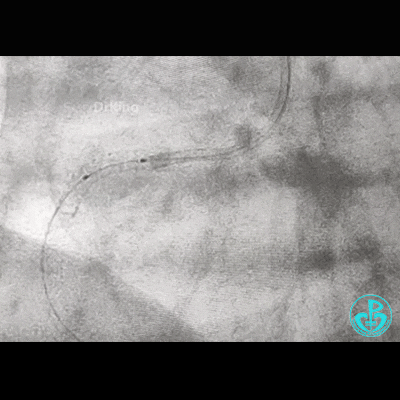

重进导丝,比较顺利!3.5×15mm球囊仍不能通过支架近段!再进一根导丝,还不行!

导丝怎么扩右冠近段弥漫性病变中远段闭塞顺利开通并植入支架,哪知道故事才刚刚开始!!!_https://www.jmylbn.com_新闻资讯_第11张

考虑导丝可能从支架钢梁外进入,故调整GC,把两根导丝均Knuckle进入,再进球囊!不行!